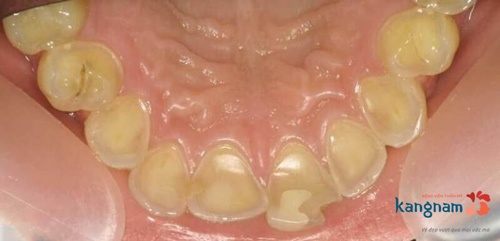

Hình ảnh trước và sau khi lấy cao răng của chị Hoa (Hà Tĩnh). Chị chia sẻ rất hài lòng về vế quả sau khi lấy cao răng và không cảm thấy nhức buốt